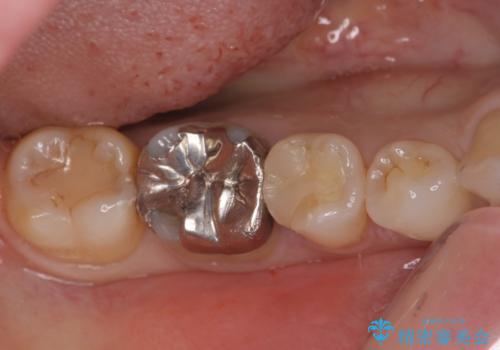

銀歯のやり替え セラミックで白い歯に

銀の詰め物を白い物にしたい